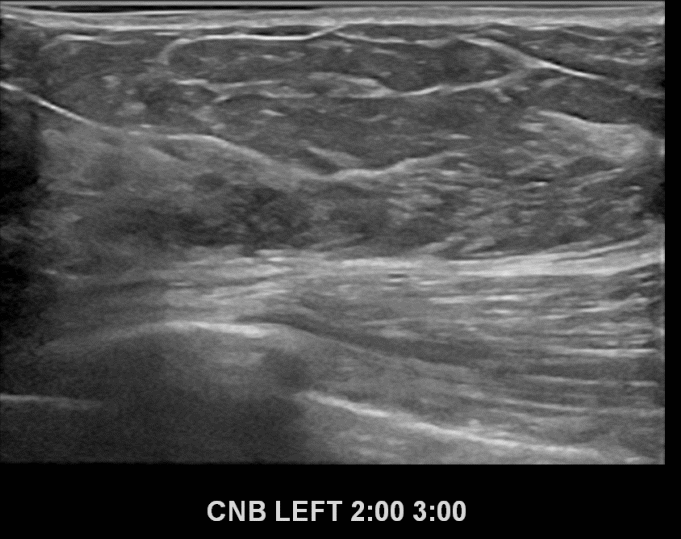

아산유외과개원후 684번째 유방암진단

상기환자 외부건진상이상소견으로 내원하신 70대여성분으로 좌측유방

의심스러운 혹 조직검사시행후 유방암 진단되었습니다